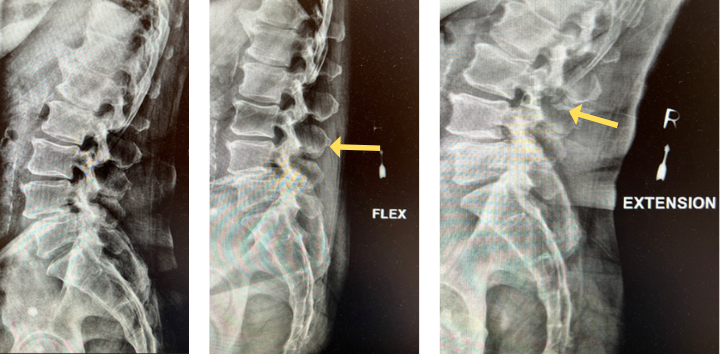

The grade 1 spondylolisthesis at L4/L5 requires both decompression at the L4/L5 level but also fusion because of the instability with motions. Here are three standing x-rays: one in the neutral position, one in flexion, and one in extensions. Notice the movement in the vertebral bodies at L4 and L5. This is abnormal motion and it can contribute to back pain and increase stenosis in certain positions. Thus, it requires decompression and stabilization with fusions.

Image 2. This shows the lumbar spine in motion. Notice the L4 and L5 level changes with flexion and extension. Notice the L2 and L3 levels do not have that type of motion. This is instability.

The herniated disc only requires decompression and removal of the herniated disc. Notice in the same flexion extension dynamic x-rays. There’s no abnormal motion at the L2/L3 level.